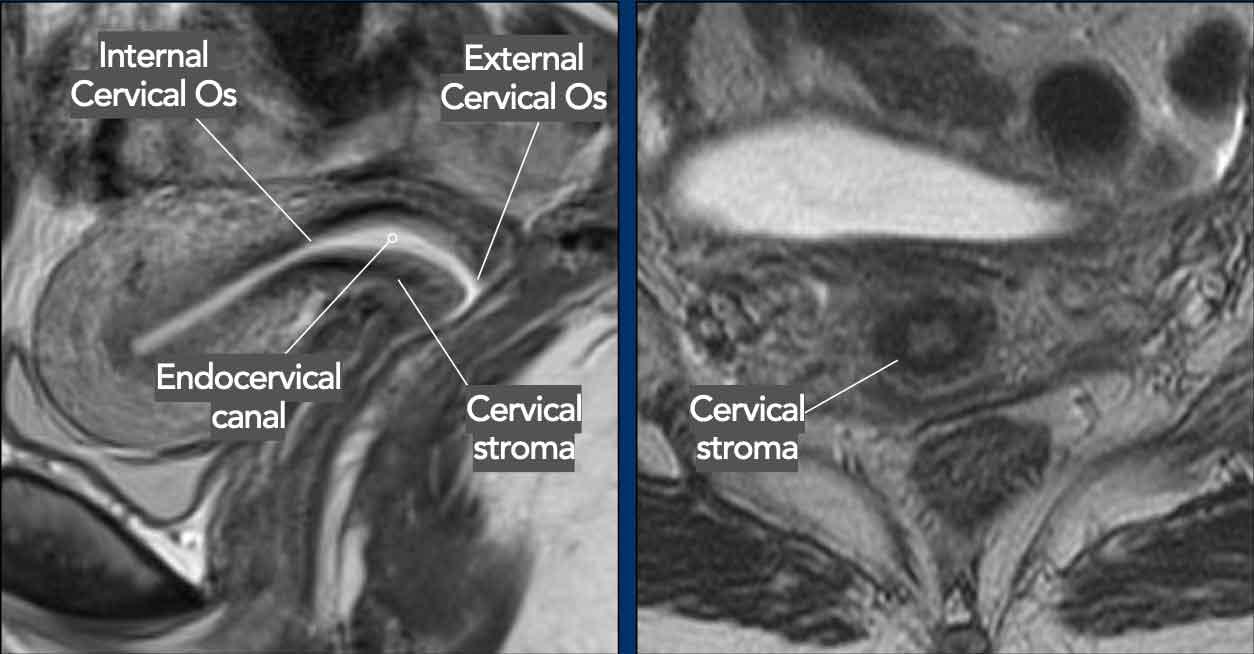

Tương tự như tử cung, cổ tử cung thể hiện các lớp cấu trúc riêng biệt trên chuỗi xung T2W MRI.

Niêm mạc cổ tử cung có tín hiệu cao.

Mô đệm cổ tử cung bình thường có tín hiệu thấp với bờ ngoài còn nguyên vẹn.

Lỗ cổ tử cung ngoài là lỗ thông giữa cổ tử cung và âm đạo.

Lỗ cổ tử cung trong là lỗ thông giữa cổ tử cung và buồng tử cung.

Giải phẫu phân vùng của tử cung và cổ tử cung trên MRI thay đổi theo độ tuổi.

Trong độ tuổi sinh sản, các lớp khác nhau của tử cung và cổ tử cung có thể nhận biết rõ ràng và phần cơ của thành tử cung có thể được tưới máu phong phú như ở người phụ nữ 30 tuổi này (hình bên trái).

Có một vòng tránh thai (IUD) trong buồng tử cung, có thể nhận biết dưới dạng cấu trúc tuyến tính giảm tín hiệu.

Ở phụ nữ sau mãn kinh, giải phẫu phân vùng trở nên kém rõ ràng hơn và mô đệm cổ tử cung, vùng chuyển tiếp và cơ tử cung xuất hiện đồng nhất giảm tín hiệu hơn trên chuỗi xung T2W, như ở người phụ nữ 70 tuổi này (hình bên phải).

Theo tuổi tác, các cơ quan sinh sản nữ dần dần thu nhỏ lại với mức độ giảm thể tích rõ rệt hơn ở tử cung so với cổ tử cung.